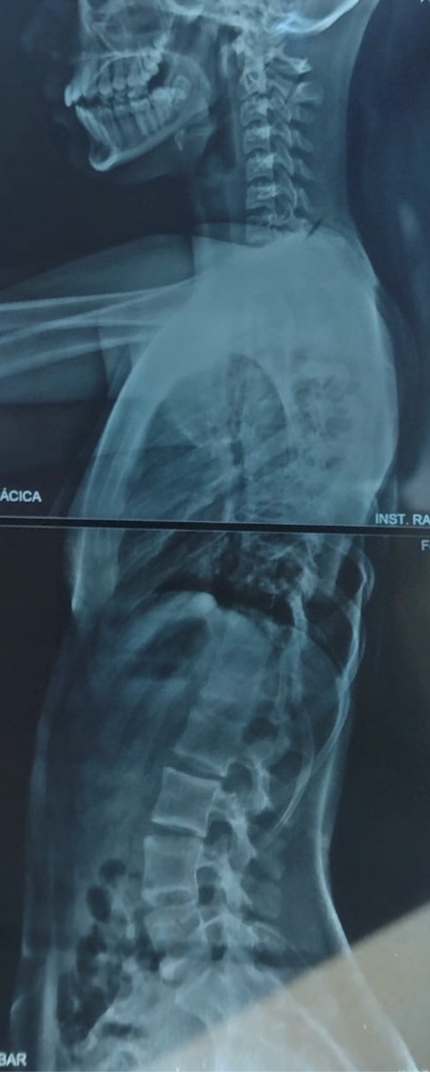

A principio del 2021 comenzamos las consultas con Dr. Pablo Fiorillo, tras unos meses de seguimiento y viendo que la curvatura seguía avanzando (+de 60⁰) decidió que la mejor opción era la cirugía.

La operación se llevó a cabo el martes 7 de junio 2021 en el Sanatorio de Niños de Rosario, duró 6 horas y constó de la colocación de una barra de fijación de cobalto y 22 tornillos. El sábado 11 de junio ya recibíamos el alta. A las tres semanas volvió a la escuela, al mes andaba en bicicleta y a los 4 meses ya hacía vida normal nuevamente e hizo su viaje de séptimo realizando todas las actividades sin preocupaciones. Destacamos el profesionalismo, la calidad humana y el excelente trato del Dr. Pablo Fiorillo para con sus pacientes. Nos brindó mucha ayuda, nos transmitió la tranquilidad, siempre presente antes y después de la operación. No tenemos dudas que nuestra hija estuvo en las mejores manos.